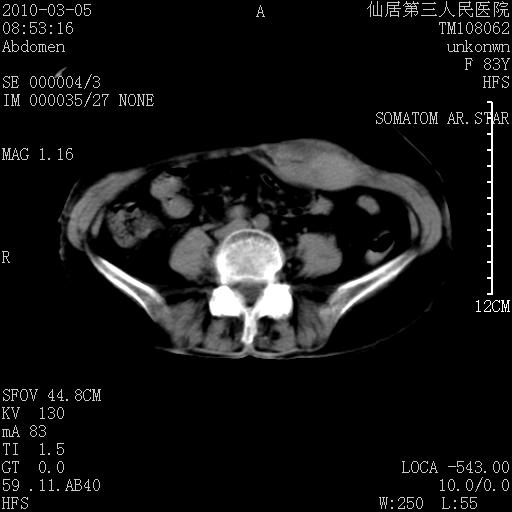

标题: CT24879:腹直肌病变。在线等。

女性,83y,腹痛一周。

有无外伤,血肿或韧带样瘤

考虑左侧腹直肌血肿,肿瘤性病变待排。

血肿,纤维瘤,子宫内膜异位都有可能。